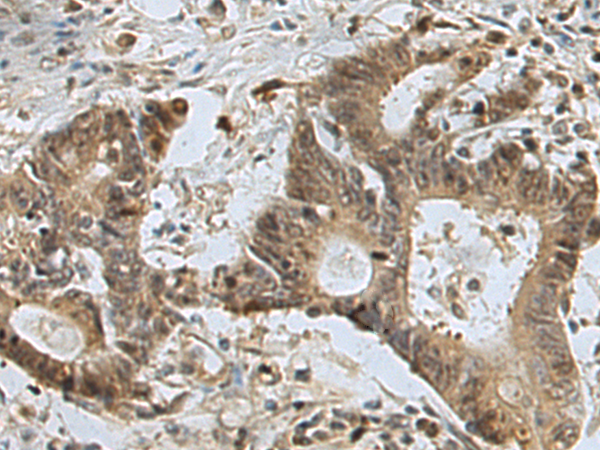

分类: 科研抗体货号: P10025别名: FDG; UNG3; HMUDG应用: IHC反应种属: Human, Mouse, Rat